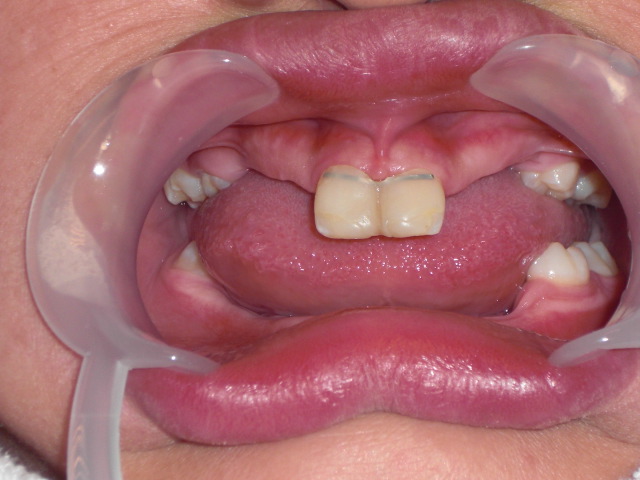

At 10 years old bracketed the two centrals and approximated the two teeth. By now patient has gotten used to visiting us and being comfortable in the dental chair. Parents and child becoming more positive and encouraged as they see the two centrals attaining a more natural position.

Retained the centrals together with a flat wire and composite. What next ?!?!

We raised the bite to a more normal vertical dimension with over crowns on the posterior molars. Observe the edentulous ridges. They have never ever hosted teeth before and cannot then be called alveolar bone.